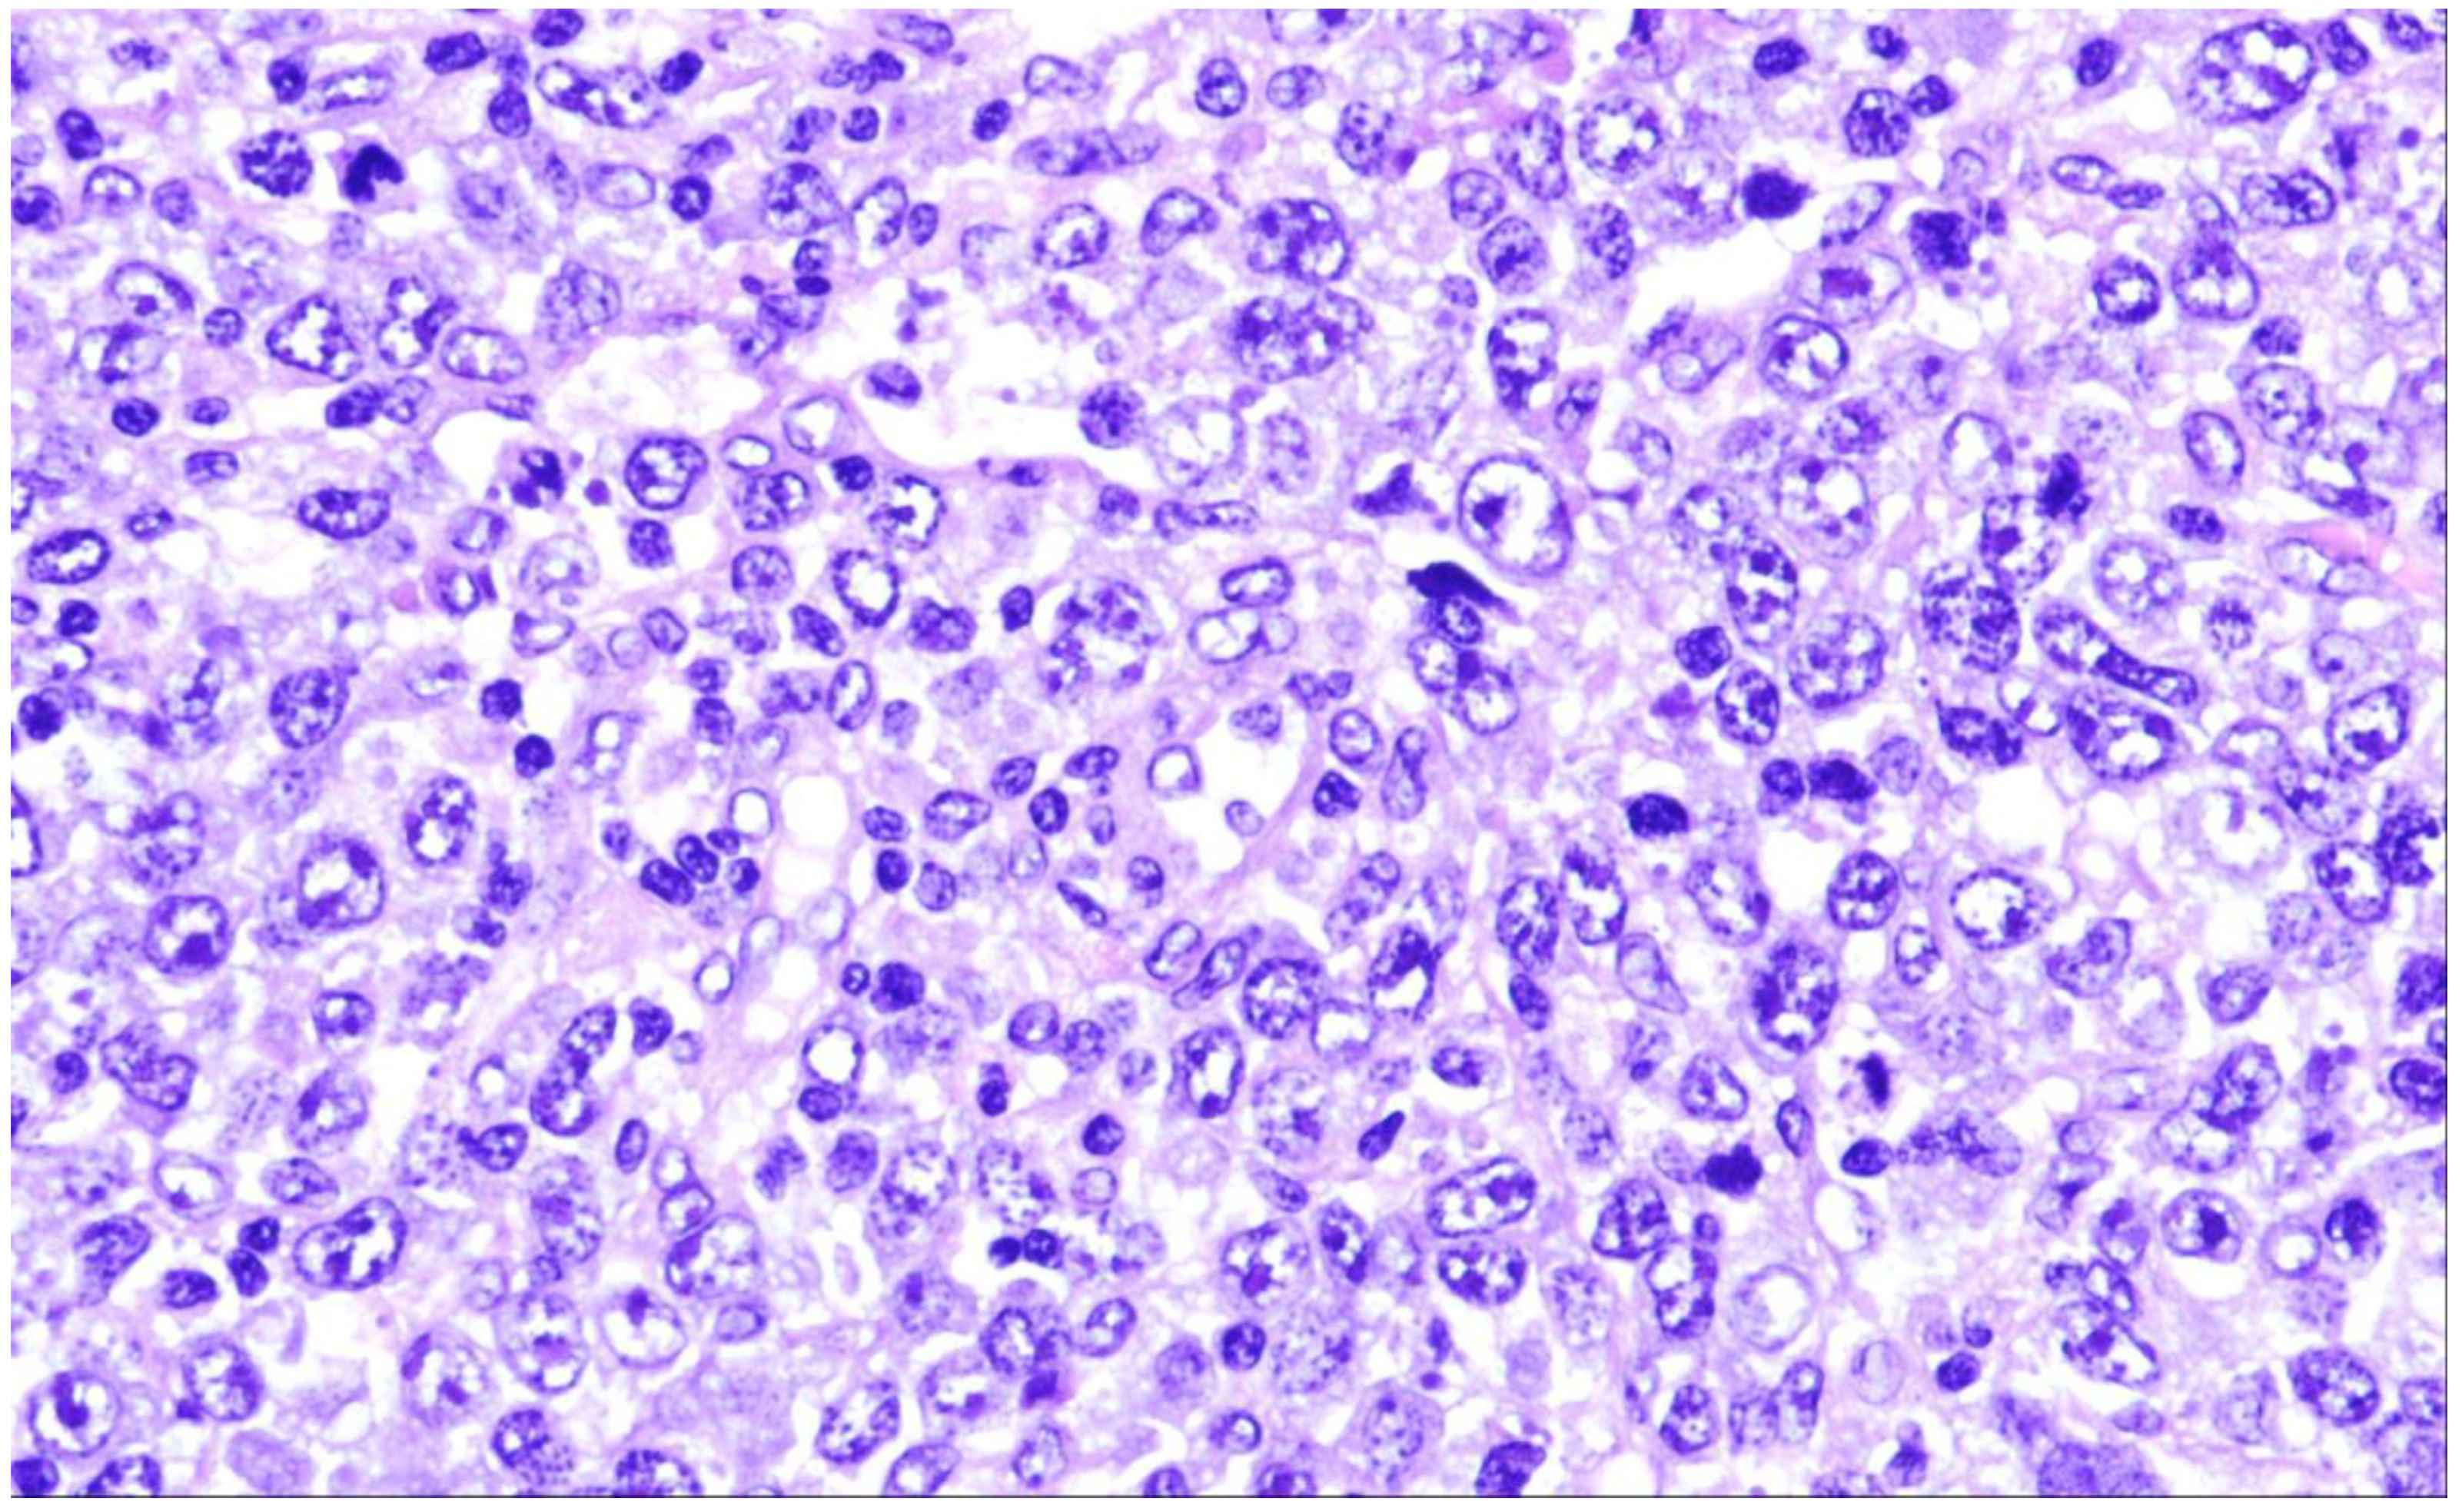

2. Diffuse Large B-Cell Lymphoma, Not Otherwise Specified

4. T-Cell/Histiocyte-Rich Large B-Cell Lymphoma

5. Diffuse Large B-Cell Lymphoma/High-Grade B-Cell Lymphoma with MYC and BCL2 Rearrangements

6. ALK-Positive Large B-Cell Lymphoma

7. IRF4-Rearranged Large B-Cell Lymphoma

8. High-Grade B-Cell Lymphoma with 11q Aberrations

9. Lymphomatoid Granulomatosis

10. EBV-Positive Diffuse Large B-Cell Lymphoma

11. Diffuse Large B-Cell Lymphoma Associated with Chronic Inflammation

12. Fibrin-Associated Large B-Cell Lymphoma

13. Fluid Overload-Associated Large B-Cell Lymphoma

14. Plasmablastic Lymphoma

15. Primary Large B-Cell Lymphomas of Immune-Privileged Sites

16. Primary Cutaneous Diffuse Large B-Cell Lymphoma, Leg Type

17. Intravascular Large B-Cell Lymphoma

18. Primary Mediastinal Large B-Cell Lymphoma

19. Mediastinal Grey Zone Lymphoma

20. High-Grade-B-Cell-Lymphoma, NOS

21. Diffuse Large B-Cell Lymphomas Arising in Immune Deficiency/Dysregulation